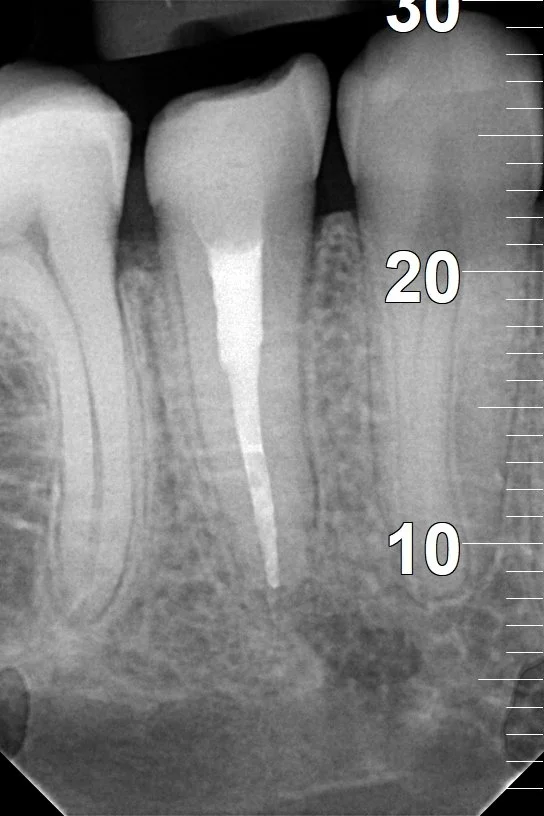

CASE STUDY IX

Usunięcie ankera zacementowanego na cement kompozytowy oraz reendo d.45 wraz z wykonaniem odbudowy adhezyjnej.